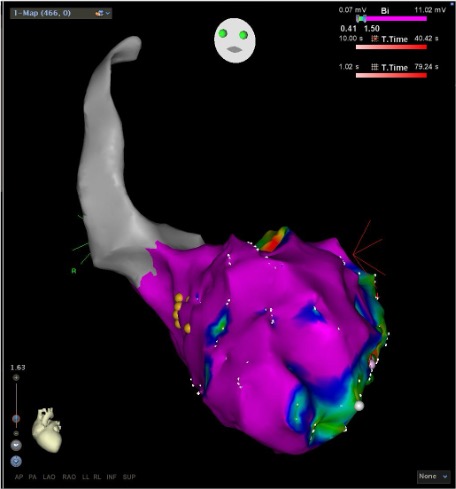

Treatment depends on the severity of VT, symptoms, and underlying heart disease. Common treatments include:

Targets and eliminates abnormal electrical pathways